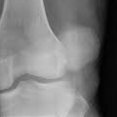

Wij komen regelmatig afwijkingen en ziekten van het steun- en bewegingsapparaat tegen. Ziekten aan het bewegingsapparaat worden vaak gekenmerkt door pijn; dieren komen niet overeind, bewegen minder of kunnen kreupel lopen. Soms is het noodzakelijk om röntgenfoto’s te maken om de oorzaak van de kreupelheid op te sporen. Hiervoor beschikken wij over een digitaal apparaat. Indien nodig kunnen röntgenfoto’s gemakkelijk met specialisten overlegd worden.

Vaak zal een bewegingsadvies gecombineerd met geschikte medicatie een oplossing bieden. In sommige gevallen zal een operatie noodzakelijk zijn om de klachten te verhelpen.